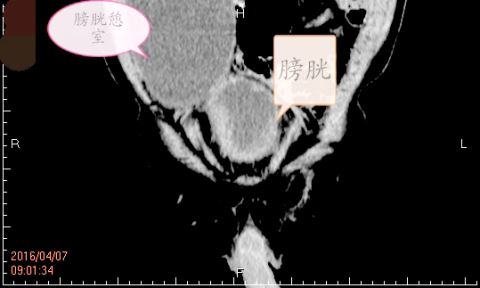

膀胱憩室CT图示。

据介绍,患者,男,67岁,因体检发现膀胱憩室。CT检查显示:患者膀胱右上方见巨大囊性包块,大小约99×65mm,与膀胱相通。据许锡荣主任介绍:膀胱憩室是与膀胱相同的向外凸出的膀胱壁,该病可引起多种并发症,如感染、结石形成、肿瘤、出血,压迫输尿管引起梗阻甚至穿孔等;巨大膀胱憩室更可能压迫膀胱颈及尿道,导致下尿路梗阻,憩室无肌缩力等导致尿液引流不畅易伴有输尿管膀胱反流,可出现一侧或双侧肾积水,最终导致肾功能衰竭。